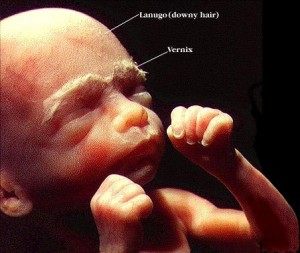

20 haftalık bebek Bebeğinizin cildi sürekli sıvı ortama maruz kaldığı için vernix caseosa adı verilen madde ile koruma altına alındı. 20 cm. ve saçları hızla uzamaya devam ediyor.